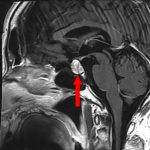

手術前1

手術前2